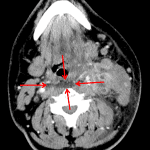

- Peripherally enhancing fluid collection deep to the left sternocleidomastoid muscle with encasement of the left internal jugular vein, which is thrombosed from the skull base to the lower neck with associated wall enhancement

- Enlargement of the overlying SCM muscle with surrounding fat stranding and thickening of the platysma muscle

- Left sided laryngeal edema and retropharyngeal edema extending from C2-C5

- Septic thrombophlebitis of the left internal jugular vein (Lemierre syndrome)

Neck abscess deep to the sternocleidomastoid muscle measuring 3 x 2.5 x 3.5 cm with encasement of the left internal jugular vein and overlying cellulitis/myositis. Thrombosis and wall enhancement of the left IJ extending from the skull base to the lower neck is consistent with septic thrombophlebitis. These findings are concerning for Lemierre syndrome. No nodules or airspace in the visualized lung apices; however consider chest CT to further evaluate for septic embolic disease.

Retropharyngeal edema without retropharyngeal abscess, which exerts mild mass effect on the pharyngeal airway.